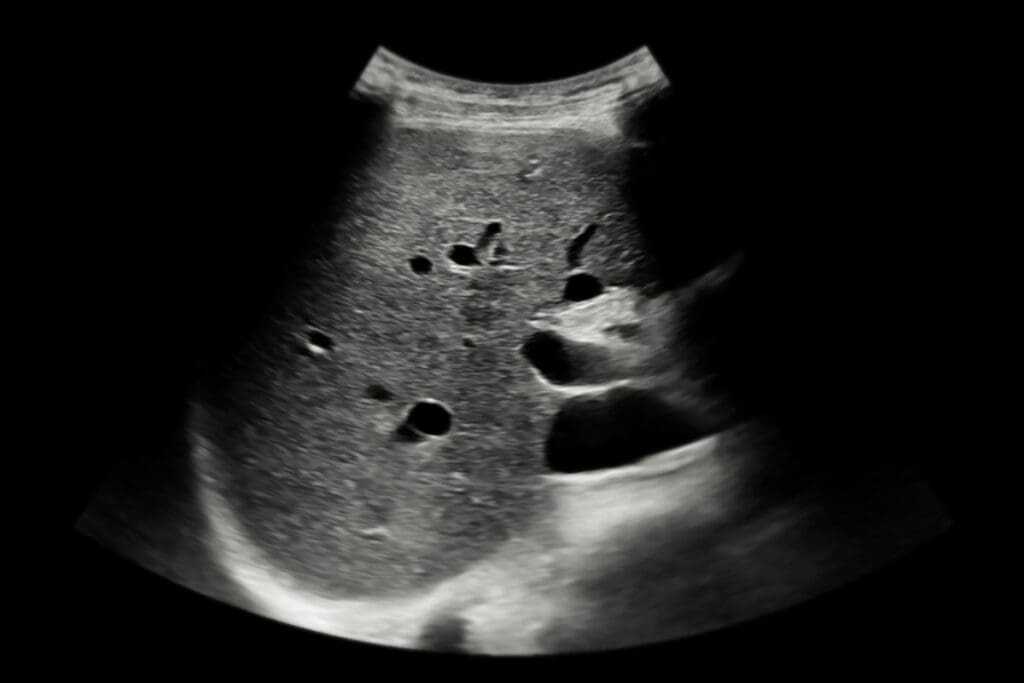

Detecting Specific Kidney Conditions

Ultrasound is also good at finding specific kidney problems that can lead to CKD. For example, it can spot polycystic kidney disease (PKD) by finding cysts on the kidneys. PKD is a genetic disorder that causes many cysts to grow on the kidneys, hurting their function.

A study in the Kidney International journal showed how accurate ultrasound is in finding PKD. It’s important for managing the condition.